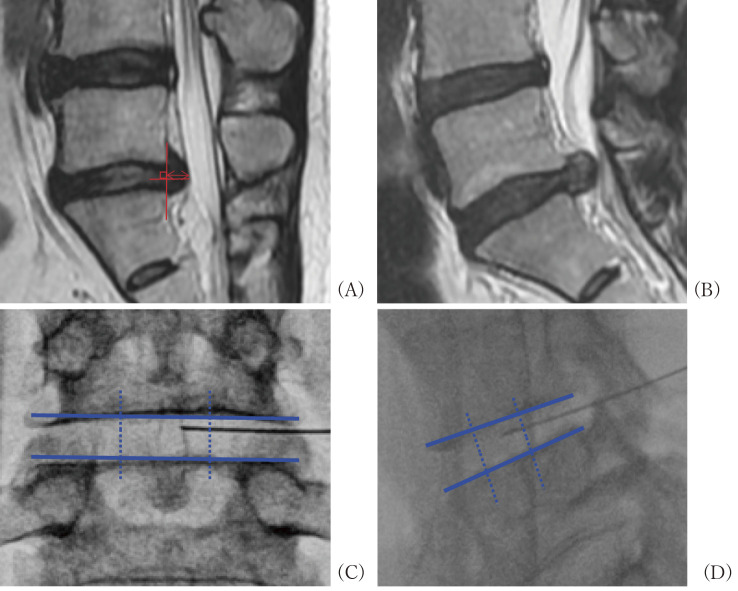

利用髁突酶进行髓核溶解术是治疗腰椎间盘突出症(LDH)的一种微创疗法,旨在减轻椎间盘压力并改善症状。在这项研究中,使用数字评分量表(NRS)测量了治疗后当天以及治疗后 1 个月和 3 个月的下肢疼痛情况。对预后因素进行了评估,将 NRS 下肢疼痛评分≥3.5 分的参与者分为改善组(I 组),评分≥3.5 分的参与者分为未改善组(N 组)。

Chemonucleolysis utilizing condoliase is a minimally invasive treatment for lumbar disc herniation (LDH) aimed at reducing intervertebral disc pressure and enhancing symptoms. In this study, lower limb pain was measured using the numeric rating scale (NRS) the day after treatment and 1 and 3 months after treatment. Prognostic factors were assessed, categorizing participants into an improvement group (I-group) for NRS lower limb pain scores of ≥3.5 and a non-improvement group (N-group) for scores of <3.5. This study included a total of 225 patients treated between April 2020 and March 2023. The mean age was 46.5 ± 16.5 years, with 151 males. The mean duration of illness was 6.2 ± 8.52 months. As of the day after treatment, 60 cases were classified into the I-group, 118 cases at 1 month after surgery, and 152 cases at 3 months after surgery. The disease duration before treatment was significantly shorter in the I-group at 1 (8.19 ± 8.74 [I-group] vs. 5.17 ± 8.04 [N-group] months) and 3 months (8.51 [I-group] ± 7.35 vs. 5.69 ± 8.87[N-group] months) after treatment. The comparison of baseline leg pain NRS shows a difference in leg pain NRS in the I-group when compared on the day after treatment (6.02 ± 2.64 [I-group] vs. 7.50 ± 1.79 [N-group]), 1 (5.13 ± 2.69 [I-group] vs. 7.58 ± 1.66 [N-group]), and 3 months (4.42 ± 2.70 [I-group] vs. 7.34 ± 1.77 [N-group]). Chemonucleolysis using condoliase for LDH can improve symptoms the day after treatment and can be a minimally invasive treatment to avoid surgery.